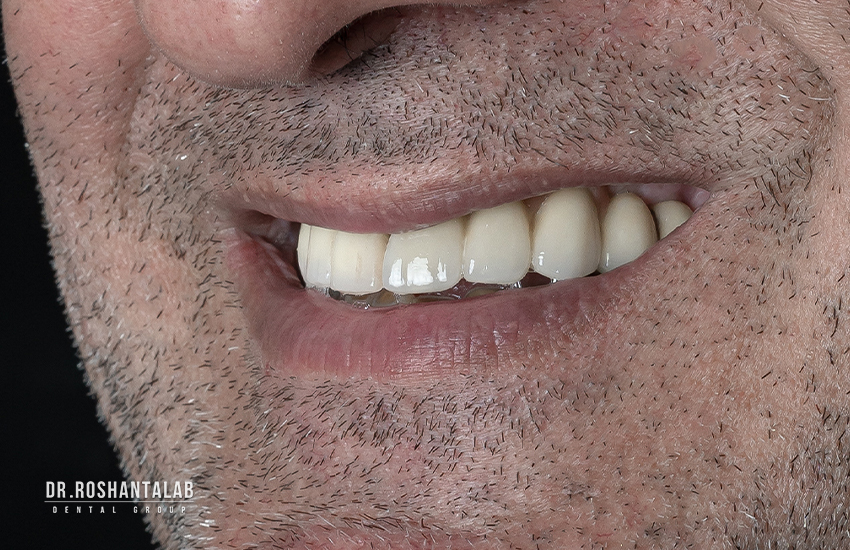

تحویل پروتز توسط متخصص پروتز

کاشت ایمپلنت توسط دکتر روشن طلب

تحویل پروتز توسط متخصص پروتز در کلینیک پاسارگاد

درمان اوردنچر توسط دکتر روشن طلب